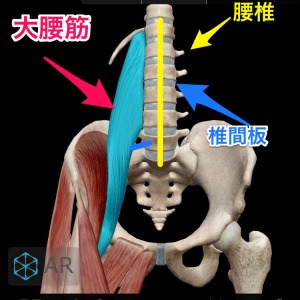

大腰筋が腰椎を圧迫

僕の経験による腰椎椎間板ヘルニアの本当の原因は大腰筋にあります。

この大腰筋ですが

主な役割:股関節を安定させる、歩く際に脚を挙げる働きをします。

起始停止:起始部は胸椎(T12)から腰椎(L1~5)の横突起で、大腿骨の小転子に停止します。

となっております。

つまり足の付け根部分と腰椎を結んでいる筋肉なのです。

腰椎椎間板ヘルニアが大腰筋の硬直等により発症するメカニズ�

硬直した大腿部が大腰筋を下方向に引っ張ったり、大腿骨頭の位置ずれが起きて大腰筋が下方向へ強く引っ張られたり、大腰筋そのものが硬直した場合に 起始部として付着している腰椎1〜5の何れかに負荷をかけてしまい圧迫が起き、押しつぶされた軟骨が変形したり 飛び出したりするのではないか?とい仮説を元に大腰筋を補正する施術をした結果98%もの方々の痛みが消失しただけでなく、飛び出していた軟骨も元に戻ったのです。

大腰筋が下方向に圧力をかけ椎間板が変形や飛び出しを起こす。